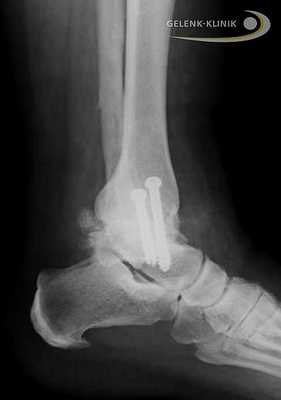

Артродез помогает восстановить безболезненность и потерянную подвижность. Данное вмешательство требует использования специальных винтов и интрамедуллярных гвоздей. Они фиксируют сустав до полной оссификации. © Gelenk-Klinik

Обездвиживание голеностопного сустава проводится под общим наркозом. Иногда используется и местная анестезия. Перед началом остеосинтеза, голеностоп освобождают от суставного хряща, то есть удаляют скользящий слой между суставными элементами голеностопа. Лишь после этой процедуры образуется прямой контакт между большеберцовой и таранной костями.

Прочное важное для остеосинтеза костное соединение, закрепляется при помощи винтов либо пластин. Артроскопические вмешательства подразумевают лишь микроскопические разрезы на коже. Сохранение мягких тканей является является важным элементов в таком лечении: только при низком рубцевании, в будущем возможно эндопротезирование.

Артродез голеностопного сустава проводится и при использовании интрамедуллярных гвоздей, которые соединяют большеберцовую кость с таранной и пяточной. Артроз нижнего голеностопа и тяжелые травмы пяточной кости требуют проведения данной методики. Применение интрамедуллярных гвоздей для обездвиживания голеностопа приводит ещё и обездвиживанию сустава между пяточной и таранной костью. © Gelenk-Klinik

Послеоперационное лечение

После артроскопической операции в течение 8 недель пациентам необходимо носить специальный ортез. В это время разрешается нагружать стопу лишь половиной собственной массы тела. При открытой операции всё зависит от формы артродеза. При использовании кости, в течение 12-ти недель стопу можно нагружать лишь 20 кг. От езды на лыжах и любых других видов спорта (искл. ходьба и езда на велосипеде) следует воздержаться как минимум один год.